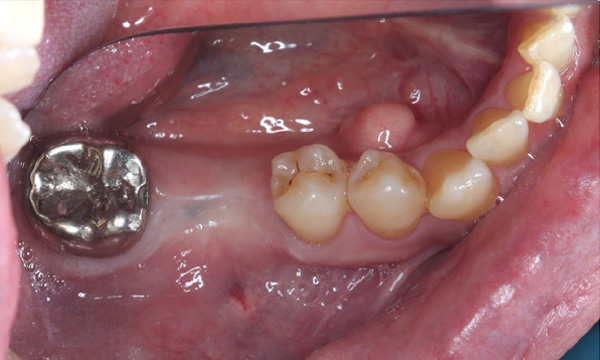

| 主訴 | 右下の歯がないのでインプラントをして欲しい |

| 治療期間 | 約6ヶ月 |

| 費用 | 600,000円 |

| 治療内容 | インプラント、骨造成、結合組織移植、セラミック修復 |

| 治療に伴うリスク | インプラント周囲炎 セラミックの破折、脱離 |